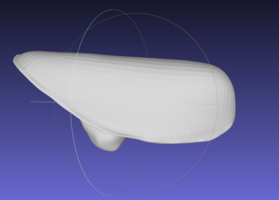

- Аллогенная деминерализованная спонгиоза, изготовленная по технологии «Лиопласт»® является биогенной и состоит только из компонентов человеческого организма.

- Всем донорам проводится аутопсия и серологическое исследование крови на сифилис и вирусы гепатитов В и С, ВИЧ.

- В Самарском банке тканей применяется оригинальный алгоритм изготовления биопрепаратов из тканей человека, защищенный патентами РФ.

- На первом этапе процесс получения имплантатов включает специальную ультразвуковую обработку тканей для удаления элементов костного мозга и жира из спонгиозы, проведения первичной стерилизации материала, вирусной инактивации.

- После первичной обработки ткани лиофилизируют, а затем герметично упакованный материал стерилизуют радиационным способом.

- II группа (21 человек) – для заполнения костной полости применяли синтетический материал «CrossBone»® (Biotech, Франция).

- Этот материал является полностью синтетическим и представлен смесью гидроксиапатита (60%) и β–трикальций фосфата (40 %).